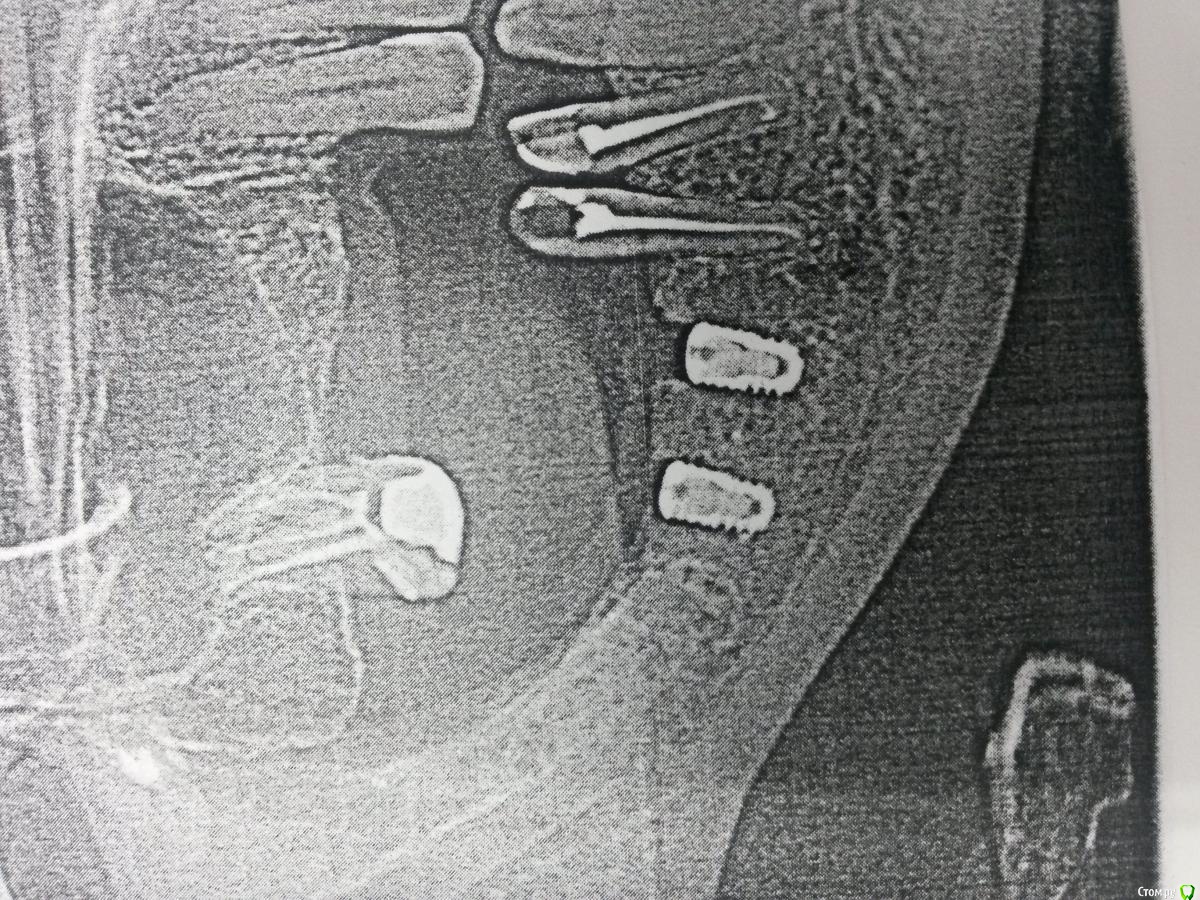

Nazim_NV86 Опубликовано 2 декабря, 2015 Поделиться Опубликовано 2 декабря, 2015 Почему он возник?Резал по гребню как обычно. Кость 1тип. 4.0х7мм. Торк 40. Шовный Викрил 5/0. Винты утоплены были в кость. Перегрев исключён. Ссылка на комментарий

Карен Аванесов Опубликовано 2 декабря, 2015 Поделиться Опубликовано 2 декабря, 2015 Ну что ж, погадаем. Инфекция раз. И верхний моляр как бэ на что то намекает. Ссылка на комментарий

gum Опубликовано 2 декабря, 2015 Поделиться Опубликовано 2 декабря, 2015 Почему вы берёте короткий имплантат и так его топите, можно и длиннее поставить вровень с костью. Периимплантит ? Грануляции нарушение стерилизации инструментов если уверены что не было перегрева и ишемии кости, мб у пациента есть соматическиепроблемы Ссылка на комментарий

alekszander Опубликовано 2 декабря, 2015 Поделиться Опубликовано 2 декабря, 2015 Почему вы берёте короткий имплантат и так его топите, можно и длиннее поставить вровень с костью. Периимплантит ? Грануляции нарушение стерилизации инструментов если уверены что не было перегрева и ишемии кости, мб у пациента есть соматическиепроблемы. Тут может на плоскостном снимке так кажется,иногда бывает при атрофии кости с одной из сторон,кажется что заглубил. У меня вопрос к топик кастеру - откуда уверенность, что не перегрел? Фрезы не тупые? Ну и гадать можно долго. Анамнез,анализы,протокол операции. Ссылка на комментарий

Nazim_NV86 Опубликовано 2 декабря, 2015 Автор Поделиться Опубликовано 2 декабря, 2015 Ну что ж, погадаем. Инфекция раз. И верхний моляр как бэ на что то намекает. моляр лечили недавно под штифтовкладку. З/о чищены. Имплант утоплен на 1мм вестибуло-орально. Стерилизацию инструментов не контролирую честно говоря. В сотрудниках уверен. Фрезы не новые точно. 3 набора в кабинете. Ссылка на комментарий

lonely_jack Опубликовано 3 декабря, 2015 Поделиться Опубликовано 3 декабря, 2015 (изменено) а какие внешние проявления? по таким снимкам диагноз бы не ставил, у нас такие на бумаге выдают самые дешевые городские поликлиники, на них и здоровые зубы с тааааакой периодонтальной щелью....обратите внимание, что вокруг формирователя вне кости - "периодонтальная щель". Может, артефакты? Изменено 3 декабря, 2015 пользователем lonely_jack 1 Ссылка на комментарий

Nazim_NV86 Опубликовано 4 декабря, 2015 Автор Поделиться Опубликовано 4 декабря, 2015 а какие внешние проявления? по таким снимкам диагноз бы не ставил, у нас такие на бумаге выдают самые дешевые городские поликлиники, на них и здоровые зубы с тааааакой периодонтальной щелью....обратите внимание, что вокруг формирователя вне кости - "периодонтальная щель". Может, артефакты? снимок и вправду с городской. Всё равно на днях открою рану для ревизии. Или не стоит? Ссылка на комментарий

Andre_ Опубликовано 4 декабря, 2015 Поделиться Опубликовано 4 декабря, 2015 снимок и вправду с городской. Всё равно на днях открою рану для ревизии. Или не стоит?может, продублировать снимок, а лучше здкт, прежде чем раскрывать... Ссылка на комментарий